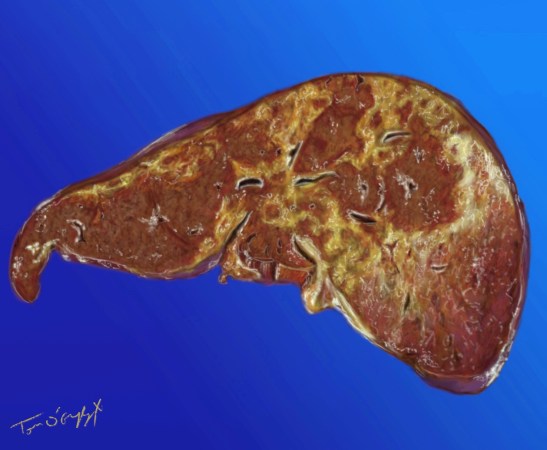

foie en autopsie avec importantes zones de nécrose en lien avec une intoxication au paracetamol

Publié le 4 décembre 2015 à 1259 × 1036 dans Intoxication au paracétamol